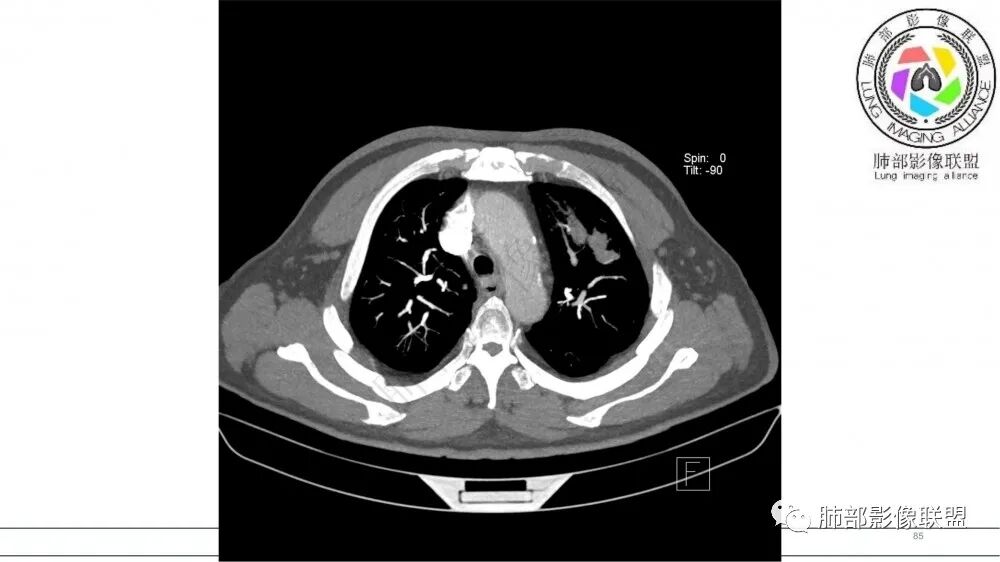

老年男性,术前检查肺气肿背景,左肺上叶结节,沿支气管蠕虫样生长,左肺门及纵隔淋巴结肿大,增强扫描不均匀强化,血管包绕,结合吸烟史,考虑小细胞肺癌。

老年吸烟男性,尖前段支气管内塑形生长,增粗蠕虫样,没有肺不张(排除鳞癌?),远端少许阻塞肺炎,增强低强化,锁定小

老年男性,吸烟,指套征,蠕虫征,阻塞性炎症不严重。可见血管穿行,密度均匀,轻度强化,首先考虑小细胞肺癌。鉴别鳞

2021年8月6日晨读病例结果:小细胞肺癌

研究报道,中心型 SCLC 经 CT 扫描后通常支气管表现为鼠尾样狭窄,肺门或纵隔肿块明显,由于肿块沿管壁生长表现为顺延支气管形态的不规则形状。病灶相对特征性影像学表现比如鸭蹼状、腊肠状、葫芦状及葡萄状改变,可以出现血管包埋,很少有空洞、空泡,较少引发肺不张,阻塞性炎症成都较轻。与一般肺癌比较,恶性程度高,侵袭力强、病灶很小就容易远处转移!Herzberg 等[19]研究指出,20%以上 SCLC 倍增时间短,预后不良。

文献报道周围型小细胞肺癌发生率为全部小细胞肺癌类型的 35%,近来有学者认为周围型病灶发生率可能更高。CT检查表现为肺实质结节或团块状,密度多较均匀,表现为浅分叶状,边缘光滑、锐利而有时可以酷似良性肿瘤。毛刺征、胸膜凹陷征与空洞、钙化少见,周围血管集束征表现为阴性,出现推移让位等情况。文献报道,增强扫描周围型肿块常表现为“沼泽地样”轻中度强化,增强后密度较低略为均匀,出现小片稍低模糊坏死 。